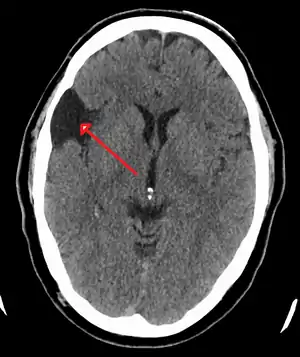

Arachnoid cyst as seen on a CT image of the brain

Axial CT showing a typical arachnoid cyst left temporal